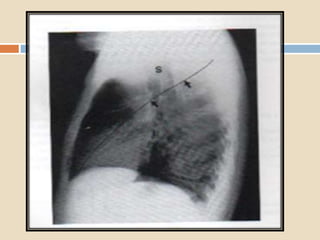

 La anatomia segmentaria del LII : superior,

basal medial, basal anterior, basal lateral,

basal posterior.